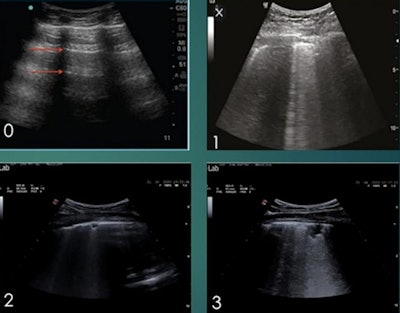

The study was based on lung ultrasound scans of 52 patients with confirmed COVID-19 cases who were admitted to the Pavia hospital between March 15 and April 29. Sabatini and colleagues performed lung ultrasound scans on the patients, then used those scans to calculate lung ultrasound scores.

Patients with worse lung ultrasound scores at admission were more likely to experience a continued worsening of their clinical condition. Patients with the worst score in three different lung sections had a six times greater chance of experiencing worsening outcomes.

Conversely, ultrasound findings improved as patients recovered. The proportion of patients with severe disease decreased significantly among patients with a second ultrasound scan after 10 days in the hospital -- a finding that "underlies the importance of lung ultrasound for patient monitoring," Sabatini said.

Researchers assigned a lung ultrasound score of 0-3 corresponding with disease severity for 14 unique lung sections. Image courtesy of Umberto Sabatini and the ASA.While the new research focused on the use of lung ultrasound, Sabatini praised ultrasound's other merits, too, especially its use for abdominal imaging. Based on his experience, he thinks the modality will be a staple for physicians long after the pandemic is over.